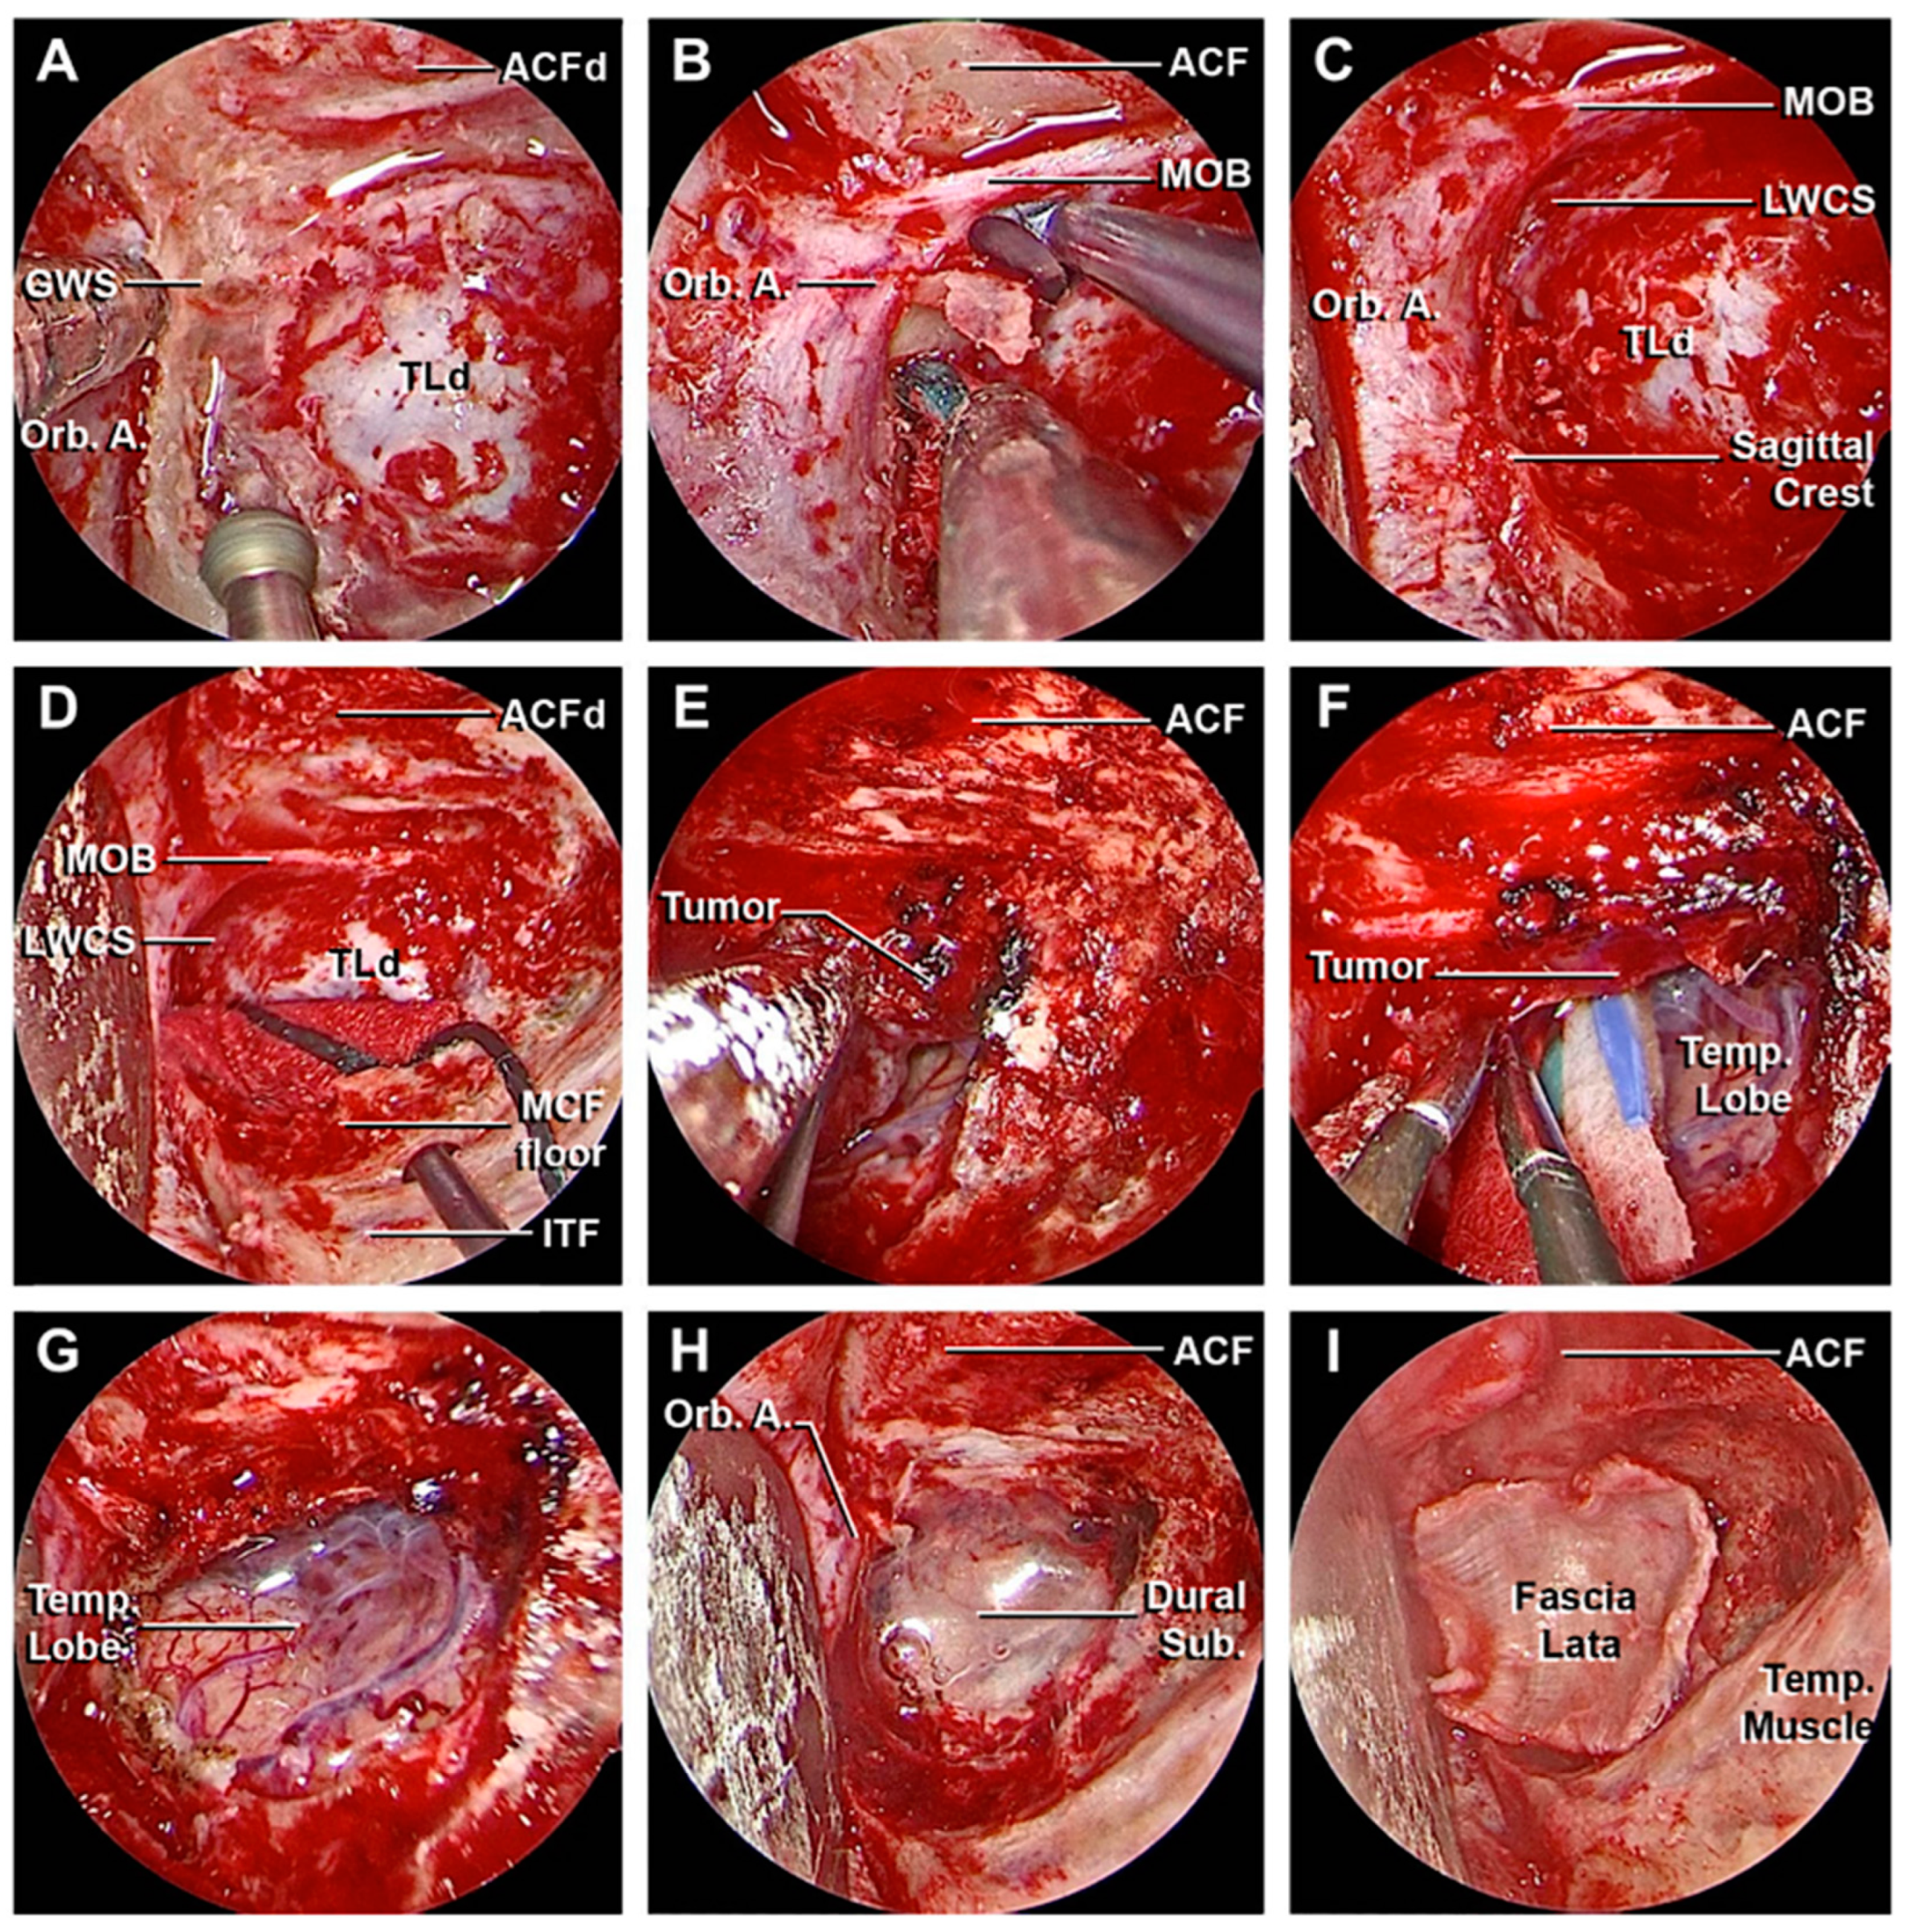

3.1. Step-by-Step Dissection

3.1.1. Craniectomy

3.1.2. Access to the Middle Fossa and Petrous Apex

3.1.3. Access to the Lateral Wall of the Cavernous Sinus and Anterior Clinoidectomy